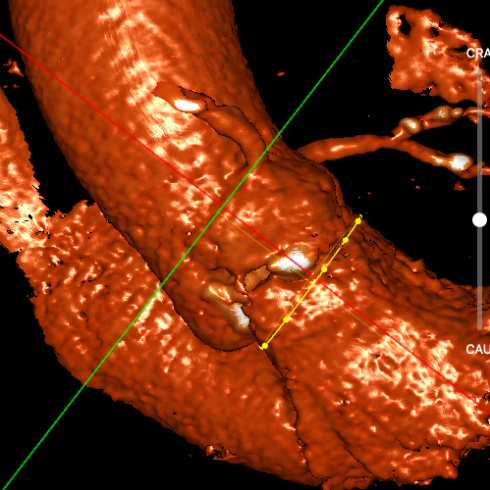

武汉协和董念国团队对该病例进行了缜密探讨,该病例为老年男性,主动脉瓣中重度狭窄,术前左室舒张功能减低。患者病例CT和心超数据显示瓣环周长:90.2mm,瓣下4mm流出道周长:97.5mm,窦部空间相对小,单纯无冠瓣瓣叶钙化,三叶瓣。左冠风险较高,缜密分析瓣叶遮盖率>50%,术中可能存在阻挡风险,需要术中球囊扩张时仔细辨认,并准备冠脉保护策略。综合评估考虑右股动脉更适宜为主入路。经过团队严谨的评估及充分的讨论,决定先行25mm球囊预扩并进一步确认冠脉风险,并准备TAV29和TAV32规格的ProStyle预装式可回收TAVR系统。

左冠评估

右冠评估

瓣环切线位窦部空间

工作位1(共平面/左冠切)

工作位2(无窦切线/左右重叠)

腹主-股动脉入路

主动脉弓降入路